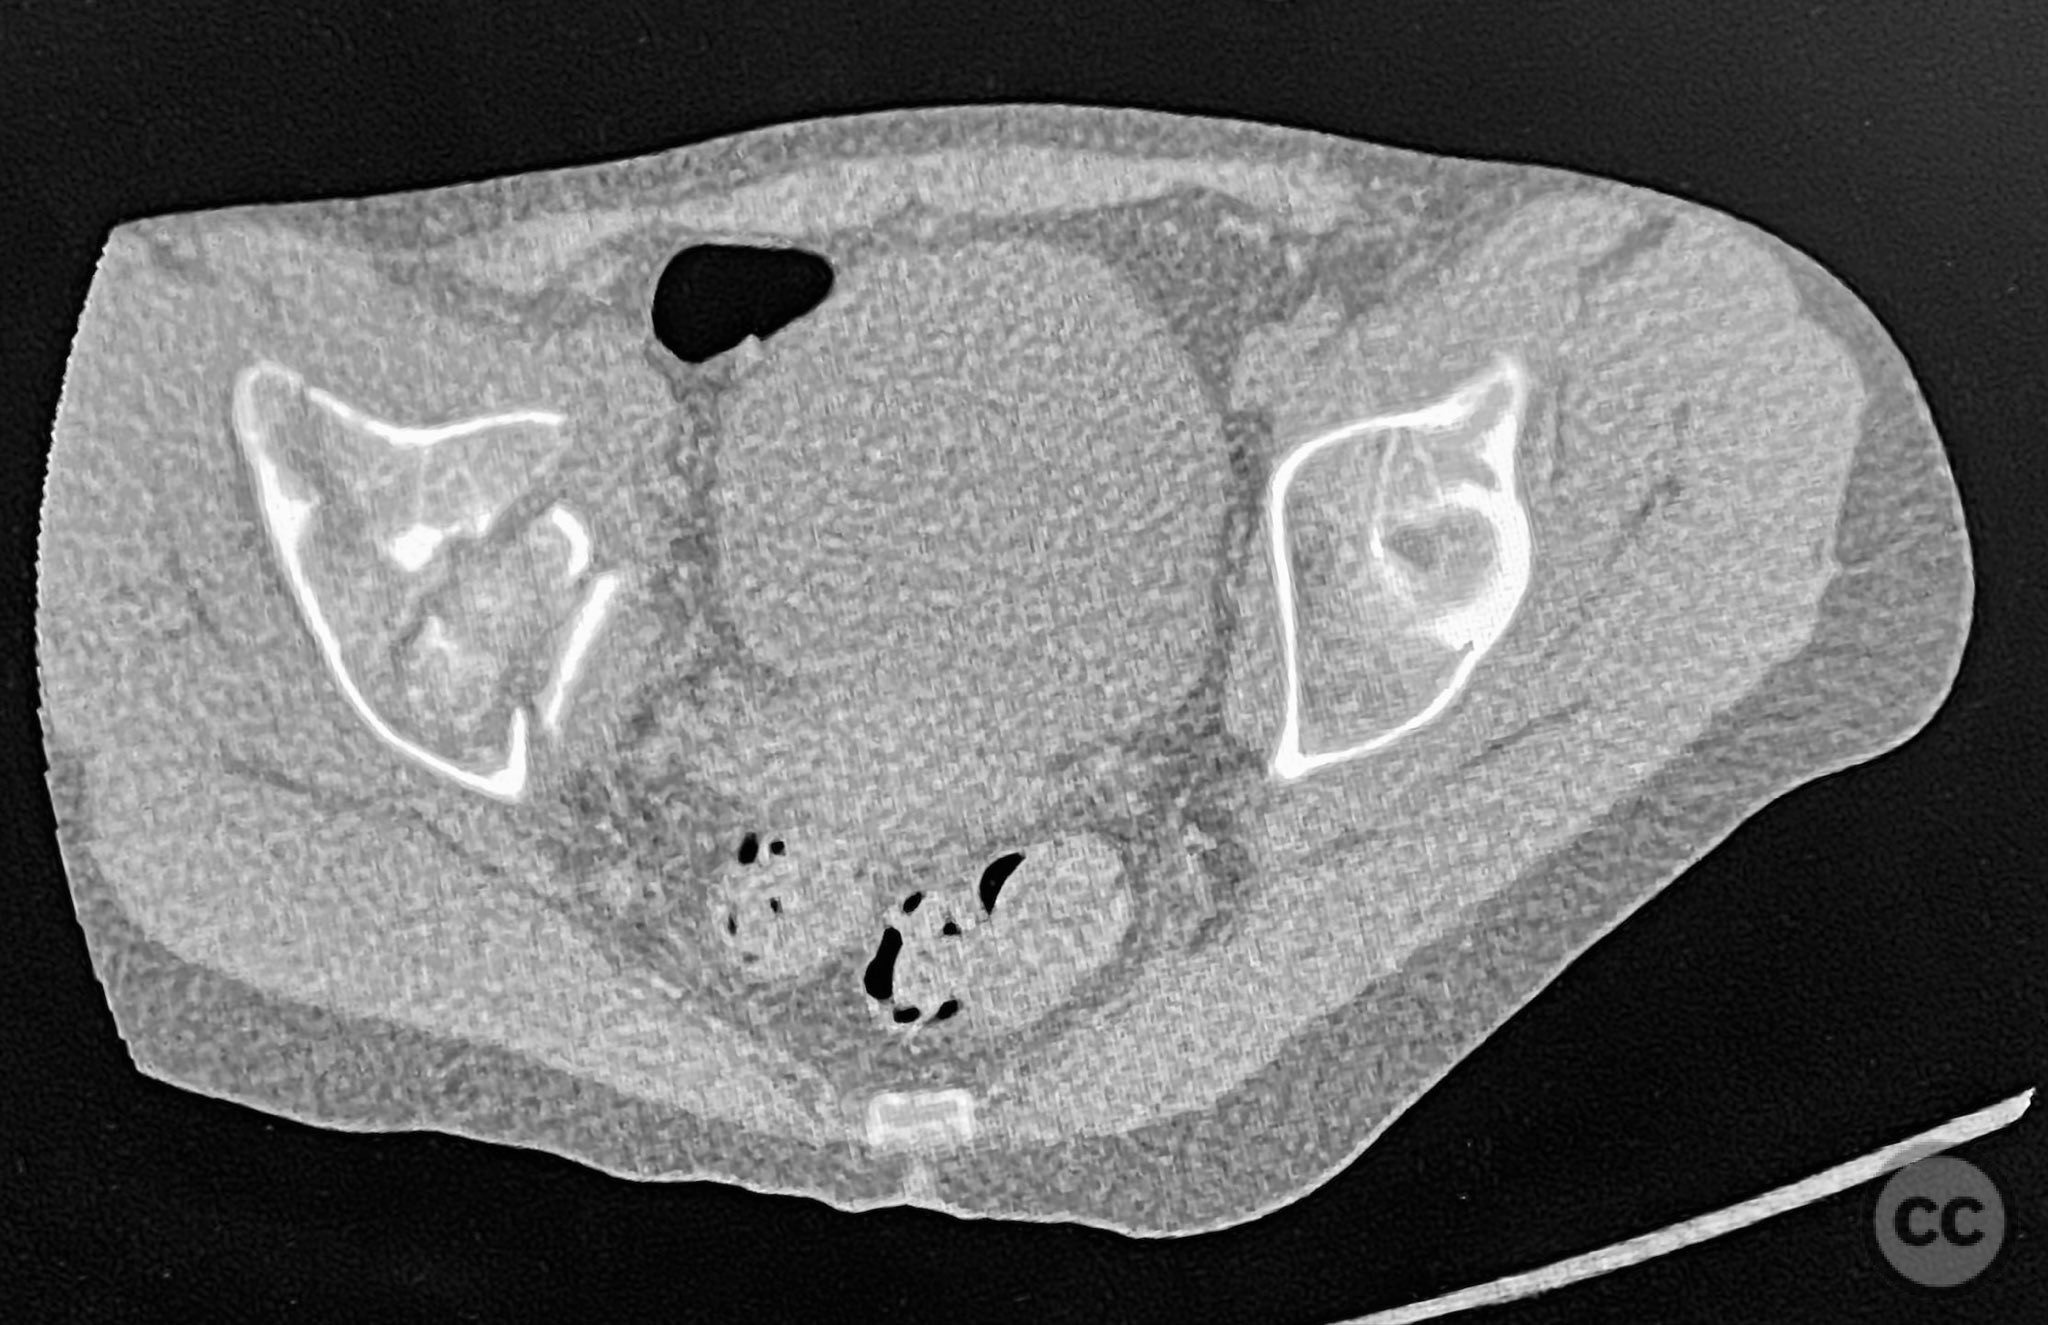

Clinical and radiological findings:  The patient sustained an acetabular fracture with a rare posterior medial dome impaction fragment, as demonstrated on AP pelvic radiographs obtained in skeletal traction. Surface renderings and axial CT images revealed multiple incomplete fracture lines, including a rhomboid-shaped cortical fragment adjacent and proximal to the anterior column/wall fragment. Coronal and sagittal reconstructions further delineated the impacted articular fragment and its relationship to the surrounding acetabular dome. The fracture pattern is classified as AO/OTA 62B3 (associated both-column fracture with dome impaction).